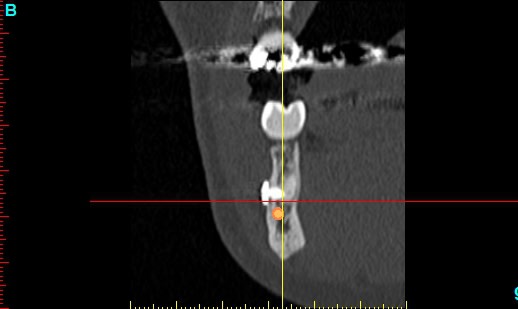

Patiente 58 ans à eu une chirurgie à visée esthétique et "fonctionnelle" adressée pour détartrage en urgence...je ne suis pas spécialiste mais je trouve que la greffe mentonnière est très bof

lésion apicale sur 42 risque de contamination sur la vis en regard..

j'ai demandé un scan en urgence.

Nous sommes d'accord pour la chirurgie mais secteur 4 il y a 2mm être là plastie et la mdble, ça ne me fais pas rêver

La chirurgie à 6 mois

Nous sommes d'accord pour la genioplastie je me suis mal exprimé ce qui m'inquiète c'est la proximité de la greffe, pardon genioplastie et de l'infection de 42, d'une part et la mauvaise liaison de la genioplastie secteur 4, mais je suis peut-être pessimiste.

N'ayant aucune donnée j'essaie d'abord de faire le tri,avant de mettre les mains dedans...je raisonne comme en implanto, quand il y a un foyer infectieux à distance proche (42) je pense qu'il y a un risque...

Plusieurs points: les vis de 15mm x 2mm qui transfixent c'est pas top, une seule plaque, qui plus est non réglable de chaque côté, c'est encore moins top. C'est une plaque de fracture.

En mandibulaire gauche c'est quoi ce fil d'osteosynthese? Un troisième fragment? En laissant l'apex de la 48 pile sur le trait d'osteotomie, je dis chapeau.

Pour la lésion de 42, ca peut être lié à la genio. Forage hasardeux? Mais je vote plus pour une lésion endo/paro